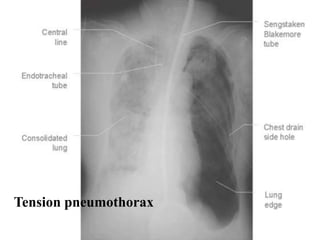

Pneumothorax

• Radiological signs:

– + shift of the heart and mediastinum to the

opposite side

– + depression or inversion the diaphragm

Tension pneumothorax